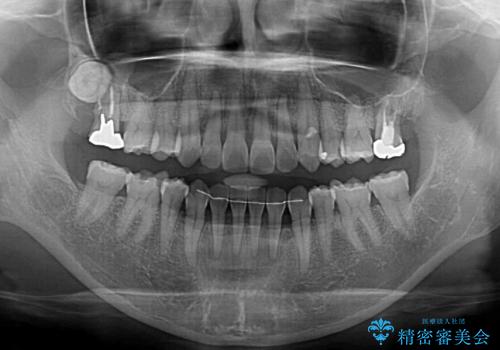

- 下顎前歯を中心に、以前行った矯正治療の後戻りが気になるとのことで来院された患者様です。

後戻りは軽度であったため、インビザライン・ライトにて治療を行うこととしました。

矯正治療後は、再度後戻りすることを極力回避するために、下顎前歯の舌側を細いワイヤーを用いて保定することとしました。